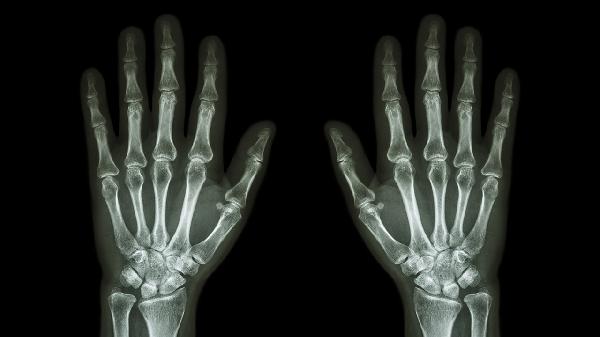

打篮球手指关节肿了怎么办

打篮球手指关节肿了可通过休息制动、冷敷处理、加压包扎、药物治疗、康复训练等方式缓解。手指关节肿胀通常由软组织挫伤、关节扭伤、韧带拉伤、腱鞘炎、骨折脱位等原因引起。

受伤初期建议抬高患肢超过心脏水平,睡眠时用枕头垫高手臂。饮食多补充蛋白质和维生素C,适量食用猕猴桃、西蓝花等促进结缔组织修复。若肿胀持续超过1周伴关节畸形或活动受限,需及时骨科就诊排除骨折可能。康复阶段可佩戴运动护指预防二次损伤。